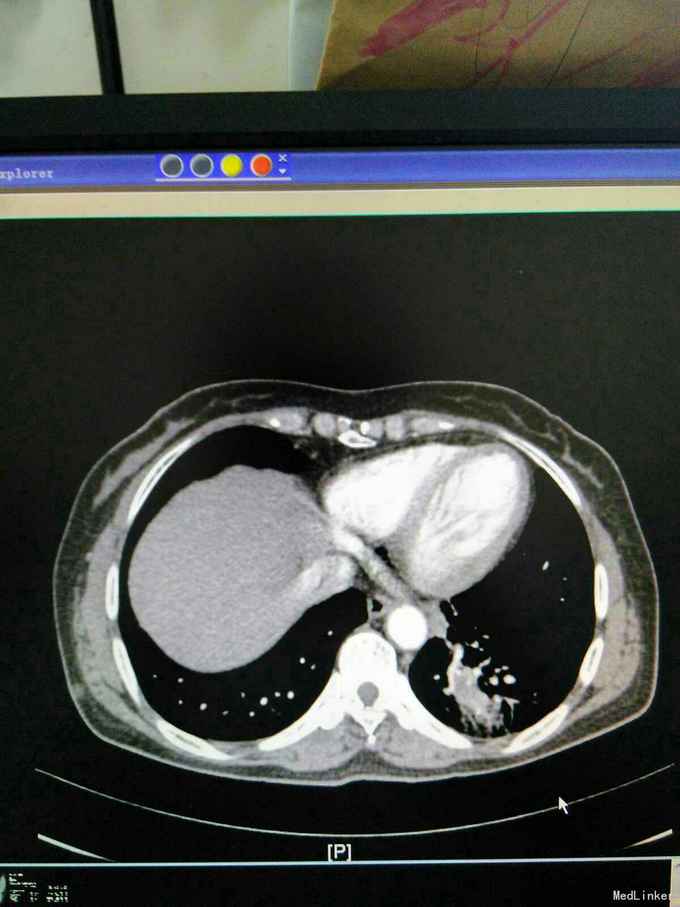

患者44岁女性,以“咳嗽咳痰间断咯血1月余”为主诉入院,入院前1月余不明显诱因出现咳嗽,呈阵发性非刺激性,咳黄白痰,每日五六口,间断咯血,色鲜红,每次10到50毫升不等,余无特殊不适,就诊当地医院摄胸部ct提示左下肺炎,予抗感染止咳化痰止血处理后症状反复,半月前复查胸部CT提示肺部阴影较前增大。

查体,神志清楚,浅表淋巴结未触及肿大,左下肺呼吸音减弱,可闻及少许湿性啰音。外院胸片示,左下肺斑片状实变阴影。

我院胸部ct增强,见左下肺病灶内见一异常供血血管,发自降主动脉,病灶周围见斑片状磨玻璃影。诊断为左肺下叶肺隔离症,转外科治疗。

患者外院胸部ct提示左下肺块影,原计划行ct引导下肺穿次活检术,我院胸部ct增强后发现,病灶为肺隔离症。遂转外科行左下肺切除术。